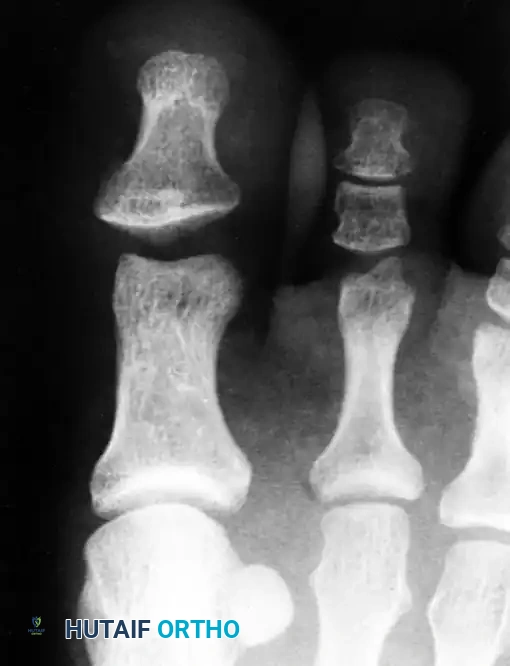

* Radiographic evidence of joint space widening after a seemingly successful closed reduction (indicating persistent plantar plate or sesamoid interposition).

Post-reduction radiograph showing the interphalangeal joint space remains wider than normal. This is an absolute indication for open reduction.

Further imaging confirming persistent widening and incongruity of the joint space despite closed reduction attempts, necessitating surgical intervention.